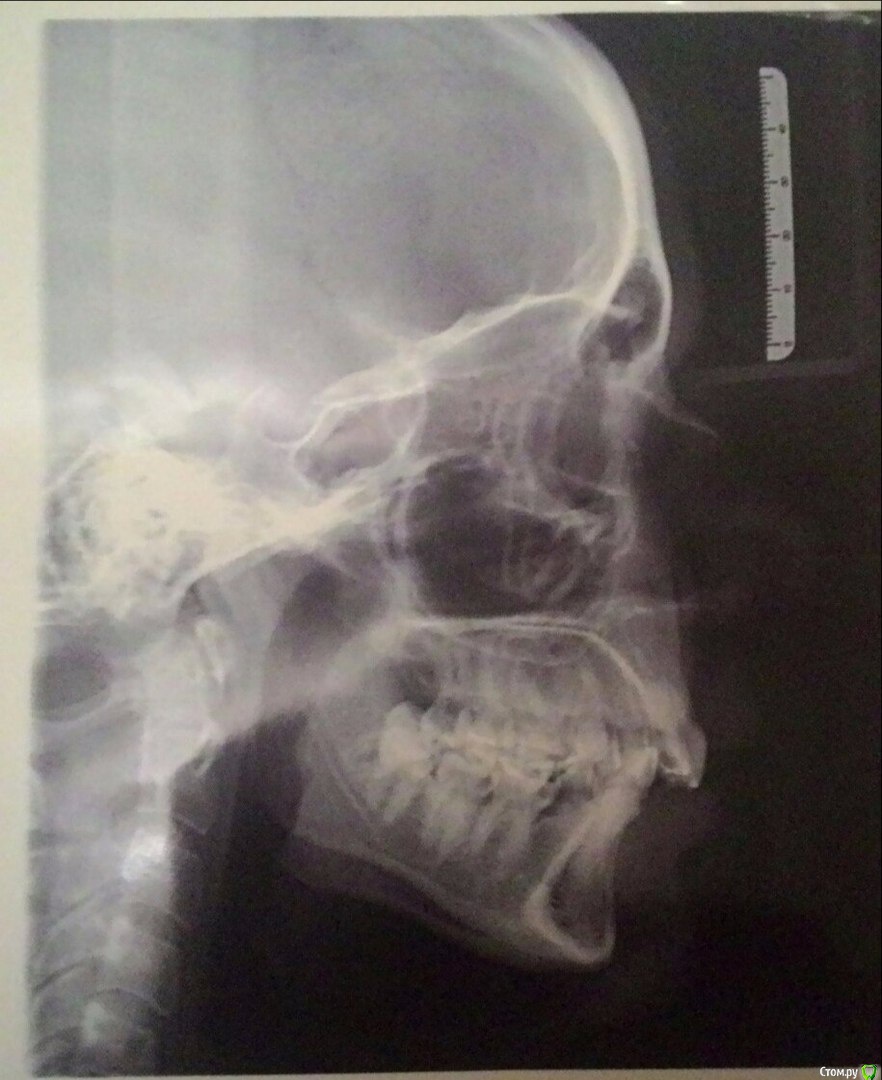

Yana guapa Опубликовано 27 декабря, 2015 Поделиться Опубликовано 27 декабря, 2015 1. какие основные жалобы сейчас?? 2. если Вы хотите предпринять действия , чтобы не ухудшилось состояние пародонта и ВНЧС(?) , то это невозможно без полноценного лечения с созданием качественных контактов зубных рядов. КАКИМ способом это будут достигаться (с хирургией или без) это надо будет решать (снимок ТРГ-размыт, остальных фото нет). 3. на ОПТГ - верхушки корней некоторых зубов уже укорочены (после первого лечения). Что будет с ними после второго лечения? Ссылка на комментарий

Telecaster Опубликовано 27 декабря, 2015 Автор Поделиться Опубликовано 27 декабря, 2015 (изменено) 1. какие основные жалобы сейчас?? 2. если Вы хотите предпринять действия , чтобы не ухудшилось состояние пародонта и ВНЧС(?) , то это невозможно без полноценного лечения с созданием качественных контактов зубных рядов. КАКИМ способом это будут достигаться (с хирургией или без) это надо будет решать (снимок ТРГ-размыт, остальных фото нет). 3. на ОПТГ - верхушки корней некоторых зубов уже укорочены (после первого лечения). Что будет с ними после второго лечения? Большое спасибо за Ваш ответ!1. Сейчас жалоб нет, я просто сильно запугана, но жалобы мои больше к психологам 2. Выкладываю скан трг (надеюсь, качество будет удовлетворительным. Скажите, пожалуйста, какие снимки нужны, я всё обязательно выложу.3.3. А чем сулит "укорочение верхушек", я не сильна в стоматологии, поэтому заранее извиняюсь, если мой вопрос покажется Вам глупым. И что кроме качественной гигиены поможет избежать "дальнейшего укорочения"? Изменено 27 декабря, 2015 пользователем Telecaster Ссылка на комментарий

Yana guapa Опубликовано 27 декабря, 2015 Поделиться Опубликовано 27 декабря, 2015 А чем сулит "укорочение верхушек", 1.если повторно лечиться - то они могут еще сильнее укоротиться, и потом зубы могут просто выпасть)) 2. http://forum.stom.ru/topic/4655-patcientam/3. обратите внимание, как сильно наклонены нижние восьмерки, особенно справа (возникает гипер контакт, идет дополнительная излишняя нагрузка на сустав)4. на ТРГ в области сустава - белое пятно ( снимок неинформативный)5. имеет ли смысл делать новые снимки? решать Вам, если планируете полноценное новое лечение (но для этого Вам нужно найти доктора, который возьмет Вас на лечение и он же направит на нужные снимки) Ссылка на комментарий

Yana guapa Опубликовано 27 декабря, 2015 Поделиться Опубликовано 27 декабря, 2015 Если сейчас я удалю нижнюю 8ку справа, не "расползутся" ли мои зубы. куда еще сильнее?)) итак уже расползлись. Поэтому сильнее вряд ли. Можно ли как-то улучшить ситуацию с корнями? нет У меня есть снимки кт вчнс КТ - это трехмерный снимок, который врач "прокручивает" и просматривает сам, оценивая объемно ткани.Положение головки сустава смотрят при сомкнутых зубах. по фото лица в профиль: да, у Вас нижняя челюсть достаточно сильно расположена кзади. Будете Вы заниматься этим вопросом или нет решать Вам (по наличию жалоб). Вероятность хирургического способа лечения высока (но это решается только после полной диагностики) Ссылка на комментарий